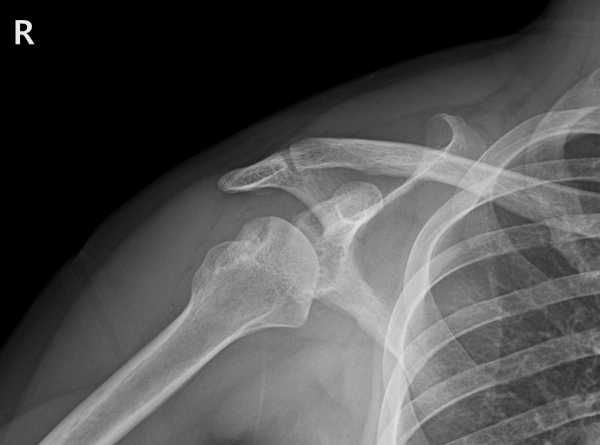

환자는 약 10년간 뇌전증을 앓고 있었고, 간헐적인 발작으로 인해 두 번의 큰 낙상을 겪었습니다.

첫 번째 낙상(2022)에는 타병원에서 전하방 관절와순파열(Bankart) 수술을 받았고,

두 번째 낙상(2025년 가을)에서는 다시 심한 탈구가 발생했습니다.

본원에 내원하여 검사를 진행했을 때 다음과 같은 소견을 확인했습니다.

재파열된 전하방 관절와순파열(Bankart) 병변(Recurrent Bankart lesion-재발성 전하방 관절와순파열)

매우 깊고 넓은 상완골두 후외측 골결손(Hill-Sachs) 결손(huge Hill-Sachs lesion-거대 상완골두 후외측 골결손)

상완골두 변형 및 결손

부분층 회전근개 파열

이 정도면 단순한 재탈구 수준을 넘어, 어깨 관절의 안정성이 거의 상실된 상태였습니다.